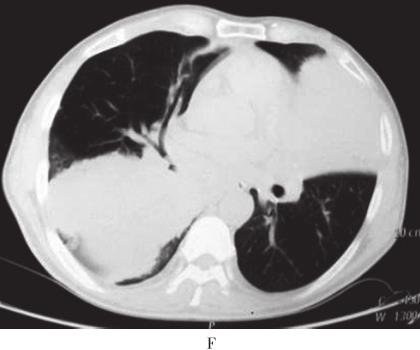

患者,男,56岁,因“活动后气短4年,加重3周”于2010年10月12日入院。入院前4年无诱因出现活动后气短,吸气时明显。3年前当地医院胸部CT检查示:双肺野内多个大小不等团片状密度增高影(图1A、B)。支气管镜下见:左上叶开口、右上叶开口及右下叶基底段开口处黏膜充血肿胀,管腔狭窄。支气管镜活检病理显示有大量淋巴细胞浸润。抗感染治疗后症状稍缓解。入院前1年上述症状加重,胸部CT示:双肺多发结节状、团块状病灶(图1C、D)。CT引导下肺穿刺活检病理示有大量淋巴细胞及浆细胞浸润,血管扩张充血,炎性渗出。诊断为双肺多发炎性肉芽肿,具体治疗不详。入院前2个月出现反复右侧鼻腔少量出血。入院前3周活动后气短加重,拟诊“双肺多发阴影性质待查”收入院。病来无发热、盗汗、咯血、胸痛、皮疹、关节痛。患者4年间多次在当地医院就诊,“怀疑肺结核、肺真菌病及肉芽肿病”,经验采用抗结核、抗真菌等治疗,具体治疗方案及疗程患者及家属叙述不清,疗效不佳。入院前半年,出现乏力、食欲下降,体重减轻4~5kg。

图1 胸部CT

A、B:2007年4月胸部CT示双肺野内多个大小不等团片状高密度.C、D:2009年10月胸部CT示双肺多发结节样、团块样病.E~G:2010年10月胸部CT示右肺下叶巨大团块状类软组织密度影,双肺弥漫性团片状浸润及实变影,纵隔内多发肿大淋巴结;胸片示右下肺团块影,双肺多发结节影

入院后体格检查:一般情况佳,双侧颈部、锁骨上、腋窝、腹股沟可触及数枚肿大淋巴结,最大直径约2cm,质硬,边界清,活动度可,无压痛。双肺呼吸音粗,可闻及广泛哮鸣音。心、腹检查未见异常,肝脾肋下未触及。入院时实验室检查:血常规:WBC 5×109/L,HGB 111g/L,PLT 368×109/L;外周血涂片:白细胞正常范围,淋巴样浆细胞约占5%,成熟红细胞呈明显缗钱样排列,血小板增多。凝血功能检查:PT 15.2秒,凝血酶原活动度74%,APTT 43.9秒;血清肿瘤标志物及自身抗体谱检查阴性;PPD试验阴性;多次痰病原学检查阴性;C反应蛋白CRP)10.8mg/L;ESR 105mm/h;血β2微球蛋白44.9ng/L;血清总蛋白106g/L,血清白蛋白35g/L,白蛋白/球蛋白0.49。胸部X线示:右下肺团块影,双肺多发结节影。胸部CT示:右肺下叶巨大团块状类软组织密度影,双肺弥漫性团片状浸润及实变影、纵隔内多发肿大淋巴结图1E和F)。支气管镜:右上叶、右中叶、右下叶、左上叶、左下叶背段支气管开口黏膜充血水肿,可见不规则隆起,向腔内生长,触之易出血,表面光滑;右下叶、左上叶支气管开口完全闭塞;于右下叶开口行支气管黏膜活检。该患者有乏力、鼻黏膜出血倾向等高黏滞血症表现,血清总蛋白106g/L,血清白蛋白35g/L,提示患者存在血清球蛋白异常增多。遂继续查免疫球蛋白定量、血清蛋白电泳及骨髓穿刺活检。结果为:IgM 87.30g/L、IgA 0.73g/L、IgG 8.14g/L、κ轻链100g/L、λ轻链3.49g/L;血清蛋白电泳及免疫固定电泳显示M成分为IgM κ,尿本周蛋白阴性。骨髓形态学示:红系增生,分类以中晚幼红为主,可见巨变、类巨变、双核红,成熟红细胞呈明显缗钱样排列;淋巴样浆细胞多见,约占23%;骨髓瘤细胞约占6%。血清单克隆IgM升高,血清免疫固定电泳检出IgM κ,外周血及骨髓中淋巴样浆细胞增多,支气管黏膜、骨髓及淋巴结活检组织标本病理均提示淋巴细胞浸润,表达CD20、CD79α、CD138等B细胞免疫表型,且轻链呈限制性表达(表1)。支气管黏膜活检示均匀一致的小淋巴细胞弥漫浸润,结合免疫组化结果,符合黏膜相关淋巴组织结外边缘区B细胞淋巴瘤(MALToma)。患者既存在骨髓侵犯,又存在单克隆性IgM分泌,故诊断为华氏巨球蛋白血症(Waldenström macroglobulinemia,WM),肺部多发占位为华氏巨球蛋白血症肺部浸润,伴局部肺不张。